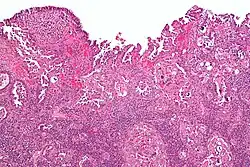

| Histology H&E of uterine serous papillary carcinoma. H&E stain. | |

Histopathologically, uterine serous carcinomas is typically characterized by (1) nipple-shaped structures (papillae) with fibrovascular cores (2) marked nuclear atypia (irregularities in the nuclear membrane, enlarged nuclear size), (3) psammoma bodies and (4) cilia. These are general findings in serous tumors which are also seen in such tumors in other anatomic locations.